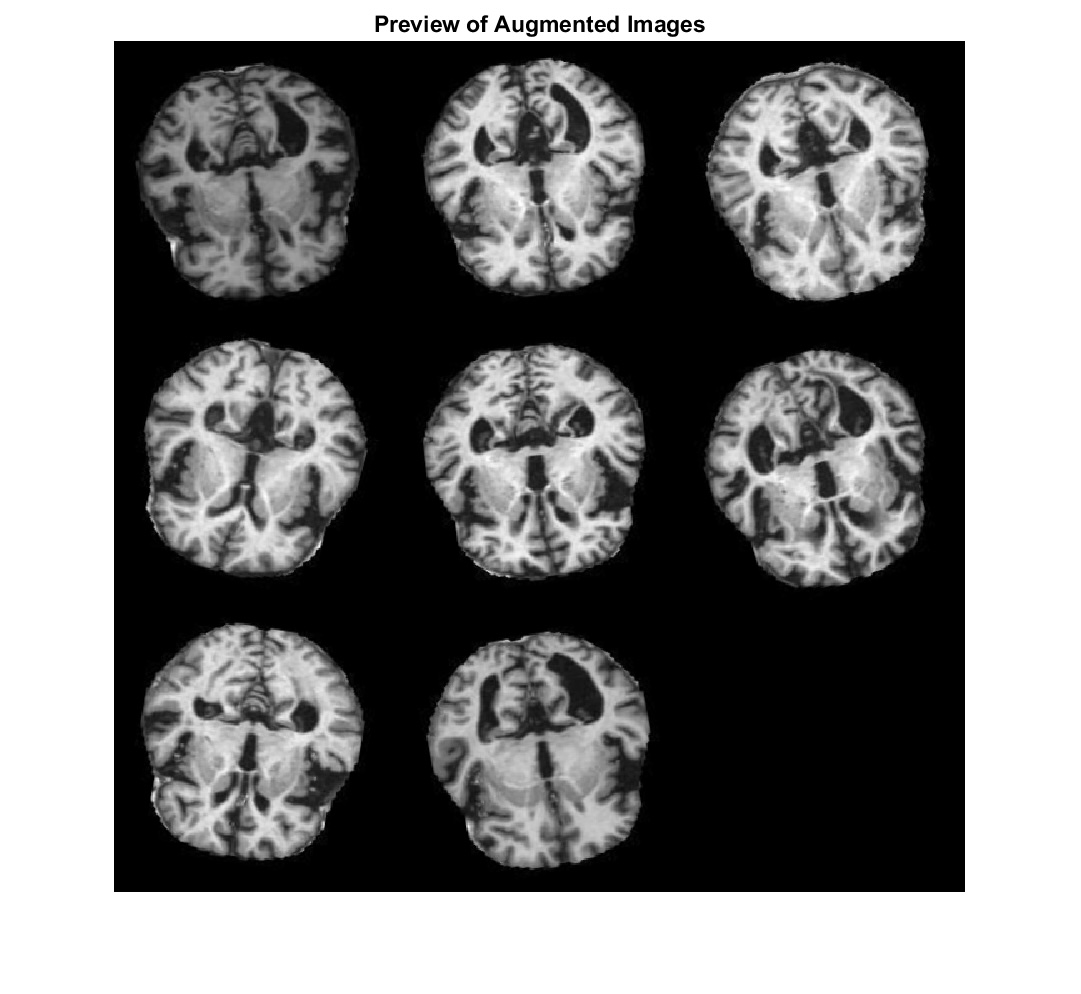

This research proposes an algorithm to identify mild in AD demented images. The core method leverages a CNN alongside a technique known as data augmentation to enhance detection accuracy as indicated in Fig. 2. Data preparation involves establishing a storage system for the images. Each image is assigned a class label, and the proportion of each class within the dataset is defined. A CNN is then built to extract crucial features from the images. The specific architecture of the CNN is established. To train the model, the images are used to train an ANN. During this process, the ANN’s specifications are fine-tuned. Finally, the effectiveness of the initial model (baseline classifier) is evaluated using a separate validation set to assess its accuracy in Alzheimer’s detection.

The baseline model is enhanced by incorporating data augmentation. This method involves creating a new dataset of modified images through random transformations like horizontal flips, slight shifts, and cropping. The ANN is applied for training of the augmented dataset. The resulting accuracy is evaluated. Next, transfer learning is employed without data augmentation. A pre-trained convolutional neural network called AlexNet is utilized [25]. One of the main strengths of AlexNet is its capability of classifying large datasets of mild AD images. This pre-trained network offers a strong foundation due to the valuable features it has already learned from a vast amount of data. AlexNet typically accepts images with a specific size (227x227 pixels) and can classify objects within numerous categories. While AlexNet is known for its speed and ability to handle smaller datasets, its final layers are replaced to adapt to the specific features within the current dataset. This modified network is then trained using an ANN with adjusted training parameters, and its accuracy is assessed. Finally, the approach combines transfer learning with data augmentation. Here, the dataset images are first augmented to the required size (227x227 pixels) and then fed into the pre-trained AlexNet model.

Fig. 2: Alzheimer detection using CNN and data augmentation.